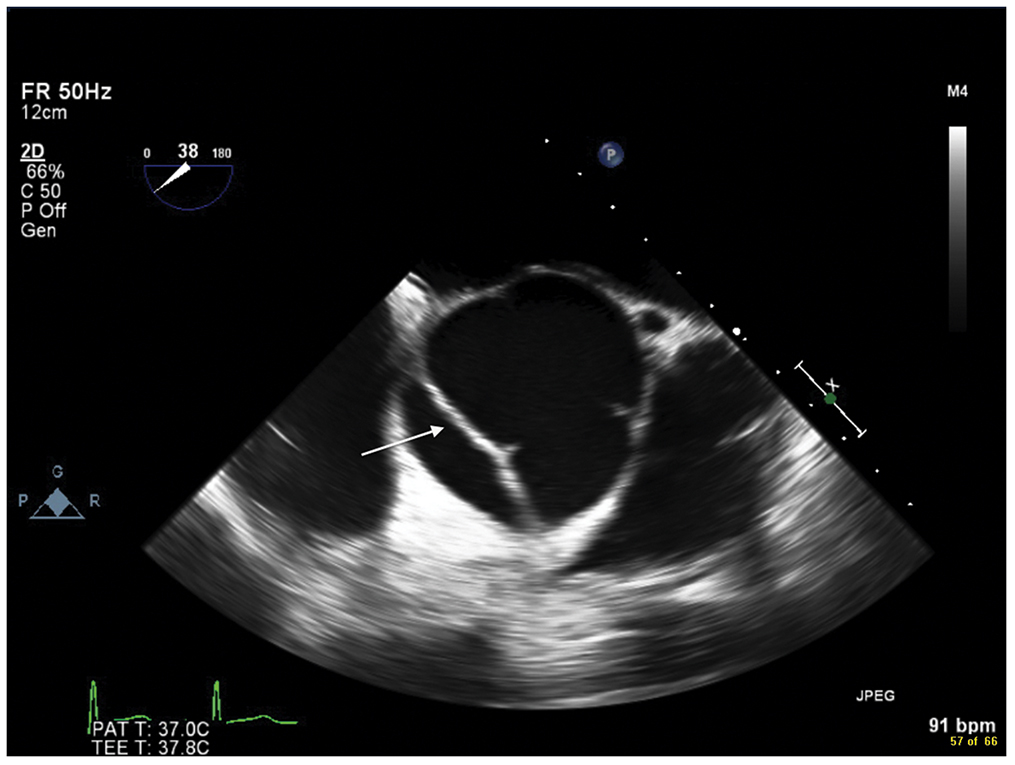

Figure 9.6.: Midesophageal Aortic Valve Short-Axis View on Transesophageal Echocardiography Demonstrating an Acute Aortic Dissection (Arrow) that Extends Proximally to the Aortic Valve in a Young Patient with Marfan Syndrome.

Midesophageal aortic valve short-axis view on transesophageal echocardiography demonstrating an acute aortic dissection (arrow) that extends proximally to the aortic valve in a young patient with Marfan syndrome.